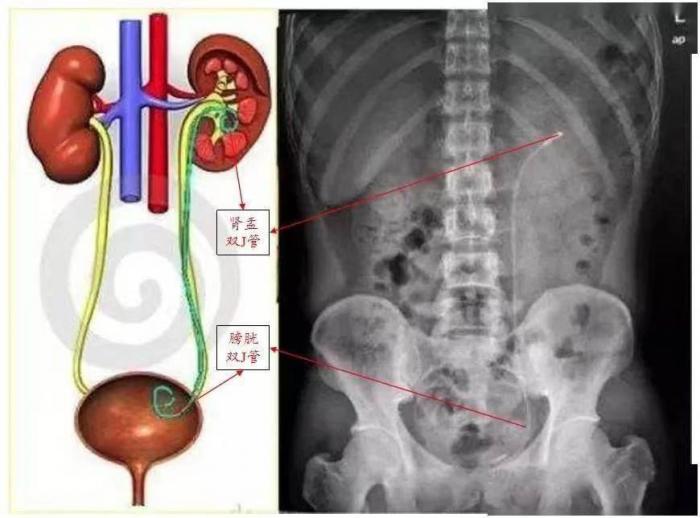

大家听过心脏支架,血管支架,鲜少听过输尿管支架。输尿管支架,因两头卷曲,形似英语字母“J”而称为“双J管”,又因每端形似猪尾被称为“猪尾管”或称D-J管,在泌尿外科手术中被广泛应用,您可别小瞧它,它一端位于肾盂,一端位于膀胱,管体贯穿整个输尿管,起到支撑和内引流的作用,保证尿液运输通畅,它可是泌尿结石患者的生命通道,适用于肾结石、输尿管结石、肾积水、肾移植、肾及输尿管良性肿瘤等上尿路手术以及输尿管狭窄的扩张等治疗过程中,它植入输尿管后能起到引流尿液、防止输尿管狭窄和粘连、堵塞的重要作用,保护肾功能。